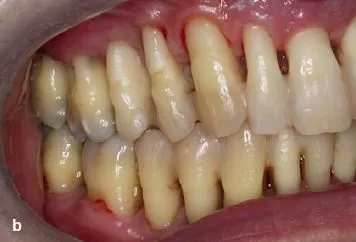

Ein Jahr nach Abschluss der aktiven Phase zeichnet sich eine positive Entwicklung ab. Die Sondierungstiefen sind deutlich reduziert (< 7 mm); deutliche Verbesserungen wurden bezüglich der Blutung (BOP 35%) und der Belagsbildung (QH 27%) registriert (Abb. 2a–c).

Auffällig ist die Verringerung der Überempfindlichkeiten, die bereits nach kurzer häuslicher Anwendung von Enamelon® Gel trotz der geringen Fluoridkonzentration eintrat. Die Reduktion der Überempfindlichkeiten war derart substanziell, dass bereits bei der ersten UPT ohne begleitende Anästhesie maschinell subgingival gearbeitet werden konnte. Der Effekt ist allerdings ? wie bei allen oberflächlich und somit auch allen vom Patienten applizierten Medikationen – nur von temporärer Wirkung [4]. Bei Verzicht auf die Anwendung von Enamelon® war daher ein zeitnaher Wiederanstieg der Überempfindlichkeiten zu verzeichnen. Für den Patienten ist ein Zusammenhang zwischen der Reduktion der Überempfindlichkeiten seiner Zähne und der Anwendung des Produktes ersichtlich; daher wendet er das Gel regelmäßig an.